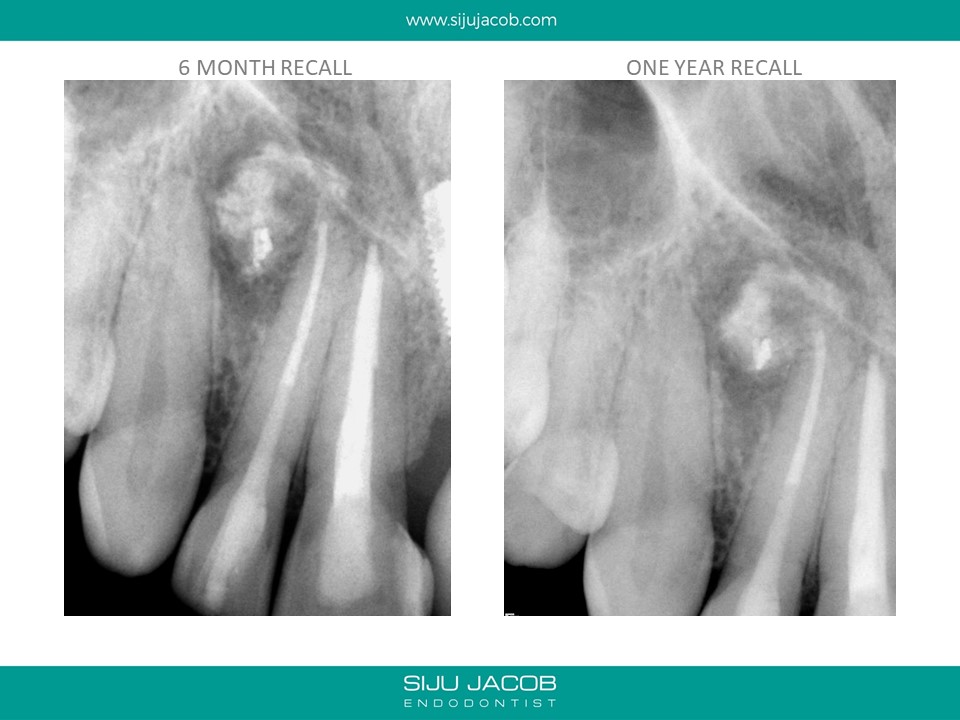

This patient was from The U.S. I re-treated a lateral incisor tooth of his while he was in Bangalore. He then went back to U.S. I received a mail from him two years later saying that the tooth we did was hurting. I thought that maybe, the lesion had recurred. I referred him to an Endodontist in the u.s who forwarded the radiograph to me. The lateral that I re-treated had healed well. It was an old central Incisor that had been treated much earlier that had fractured.